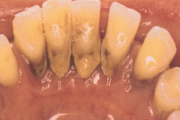

Krooniline parodontiit

Krooniline parodontiit on mikroobide poolt põhjustatud hammaste tugikudede põletik, mille tulemusena tekib progresseeruv alveolaarluu (nähtav röntgenograamil) ja periodontaalligamendi destruktsioon, igemetaskute moodustumine, igeme retsessioon või mõlemad kahjustused kombineeritult. Loe edasi »

Sümptomid:

- igemed veritsevad (19)

- igemed punetavad (21)

- ige on paistes (mädapunn)

- igemed on tursunud/vohavad (17)

- luu destruktsioon (5)

- horisontaalne luukadu (3)

- puudulik suuhügieen (5)

- igemepealne hambakivi (5)

- igemealune hambakivi (4)